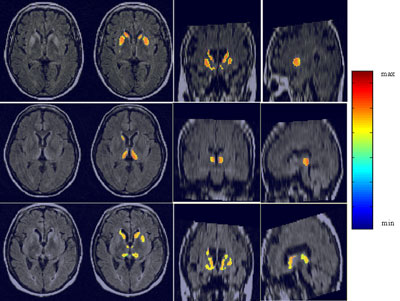

Our method used analysis of deep grey internal nuclei of the brain (namely the head of caudate, putamen and thalamus) to accurately detect human spongiform encephalopathy in multisequence MRI of the brain. T1, T2 and FLAIR-T2 MR sequences were used for the detection of intensity deviations in the internal nuclei. The use of a priori anatomical knowledge in the form of an accurately segmented and labelled atlas facilitated the precise segmentation, while a probabilistic atlas allowed intra- and inter-patient analysis. A feature detection technique based on a model of the human visual system was employed for the depiction of hypersignals. The varieties of human prion disease (sCJD vs vCJD) were differentiated using newly defined MR measures based on the lesions' topographical distribution.

Our database comprised fifteen CJD cases (ten sCJD and five vCJD) and eight healthy controls of the same age range as the patients. All patients showed abnormal intensities in the deep grey nuclei, which were correctly detected by our algorithm. We diagnosed all fifteen prion disease cases with no false positives amongst the controls. The results are robust over the patient data and in accordance with the clinical ground truth.

The caudate nuclei are highlighted as the main area of diagnosis in sCJD, in agreement with the histological data. The algorithm permitted the classification of abnormal signal intensities in sCJD patient FLAIR images with a more significant hypersignal in the caudate nuclei (10/10) and putamen (6/10) than in the thalami. In vCJD patients, we found more significant hyperintensities in the pulvinar than in the other internal nuclei, which confirmed the visually based radiological observations related to CJD. Defining normalized MRI measures of the intensity relations between the internal grey nuclei of patients, we differentiated without ambiguity all CJD cases (sCJD and vCJD) from healthy controls and further classified the CJD patients into two subgroups, sporadic and variant. This is to our knowledge the first attempt towards an automatic classification tool of human spongiform encephalopathies.

The algorithm also allowed the study of asymmetries in CJD MR hypersignals, which has long been a subject of debate by neuropathologists. Using brain internal nuclei masks, we also noted that hypersignals are inhomogeneous over the nuclei.